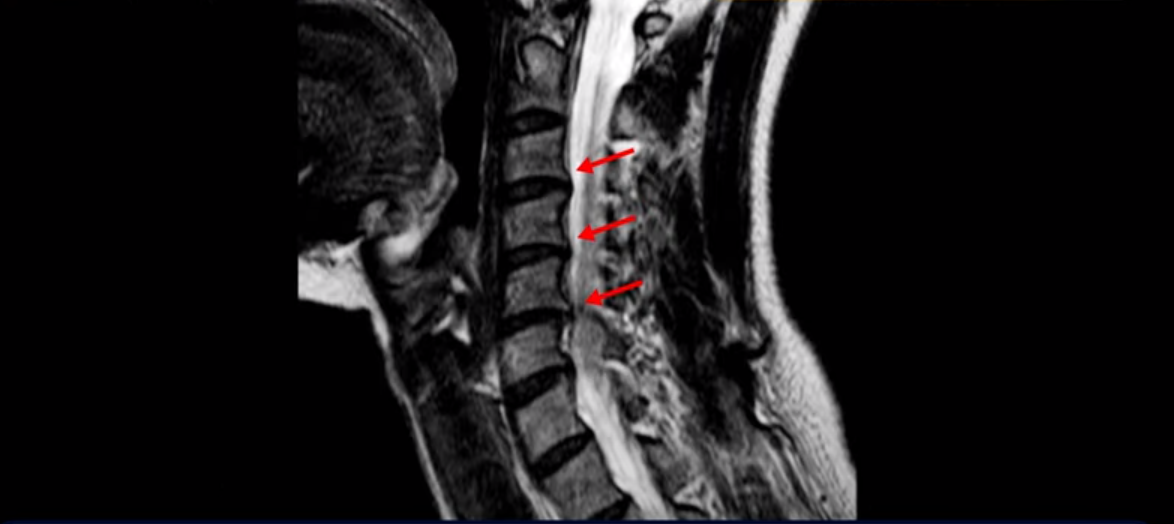

그런데 이분 목을 보시면 여러 마디의 뼈가 퇴행이 진행되어 있습니다. 뼈가 깍두기처럼 각지고 예뻐야 하는데 끝이 조금씩 변형되어 뾰족하게 자라고 있습니다.

이런 게 협착을 일으킵니다. 그래서 우선 오른쪽 신경구멍 즉 추간공을 살펴보면 맨 위의 한마디를 빼고는 다 좁아져 있습니다.

특히 5번 6번 구멍이 가장 좁습니다. 이걸 협착이라고 합니다.

사실 여러 신경 구멍이 다 좁아져 있기 때문에 정확히 어느 마디가 방사통을 일으키는지 정확히 알기 어렵습니다. 그래서 만일 수술을 한다면 정확히 어느 마디가 진짜 원인인지 파악하지 못한 채 한다면 수술이 크게 실패할 수도 있습니다. 또한 이분처럼 여러 마디가 안 좋아서 수술한 마디의 위나 아래가 상태가 좋지 않으면 유합술 후 그 위나 아래에서 또다시 문제가 생기는 인접 분절 질환이 수술 후에 발생할 수도 있습니다. 이런 정도는 알아두는 게 좋습니다.